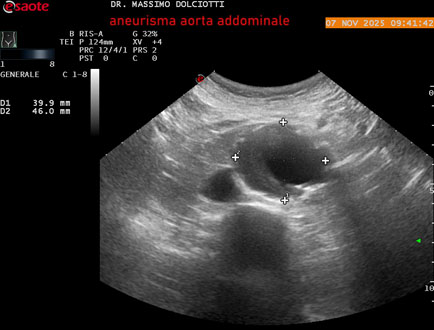

Data inserimento: 11/11/2025

Ecografia del: 07/11/2025

Strumento: Esaote MyLab Eight

Sonda: Convex Multifrequenza 1-8 MHz

Età Paziente: M 60 anni

Motivazione dell'esame: follow up per aneurisma dell'aorta addominale.

Commento all'esame: le immagini ed il video documentano la presenza dell'aneurisma dell'aorta addominale sotto-renale, con diametro antero-posteriore massimo documentato di 47 / 48 mm.

Conclusioni: aneurisma dell'aorta addominale in follow up (abdominal aortic aneurysm follow-up).

Presentazione: Dr. Massimo Dolciotti - Ancona

Elaborazione digitale: Andrea Dini - Ancona